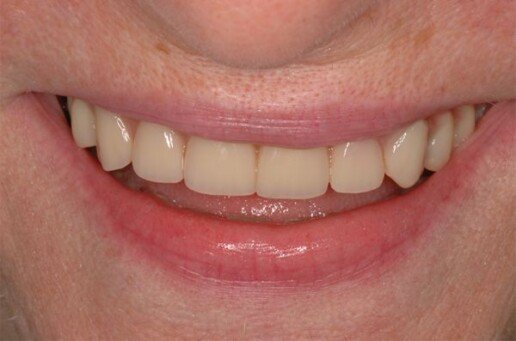

Riabilitazione totale superiore e inferiore su impianti. Gli esiti di una paradontite grave portano alla perdita totale dei denti. E’ necessario ricostruire sia i denti sia i tessuti molli e anche l’osso per il sostegno delle labbra.

Prima

Dopo